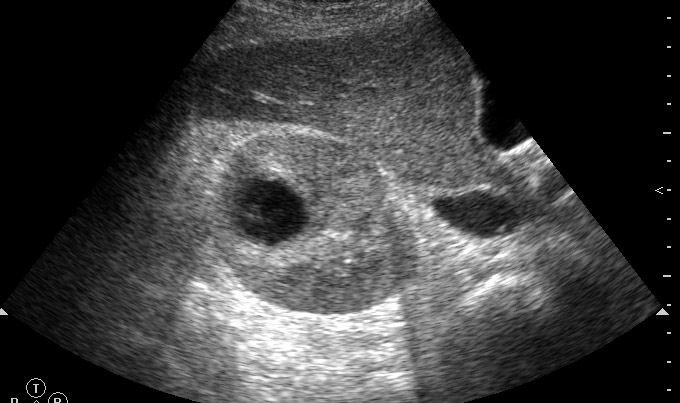

Продольное сканирование  правой почки. Почка 140х65х65 мм.